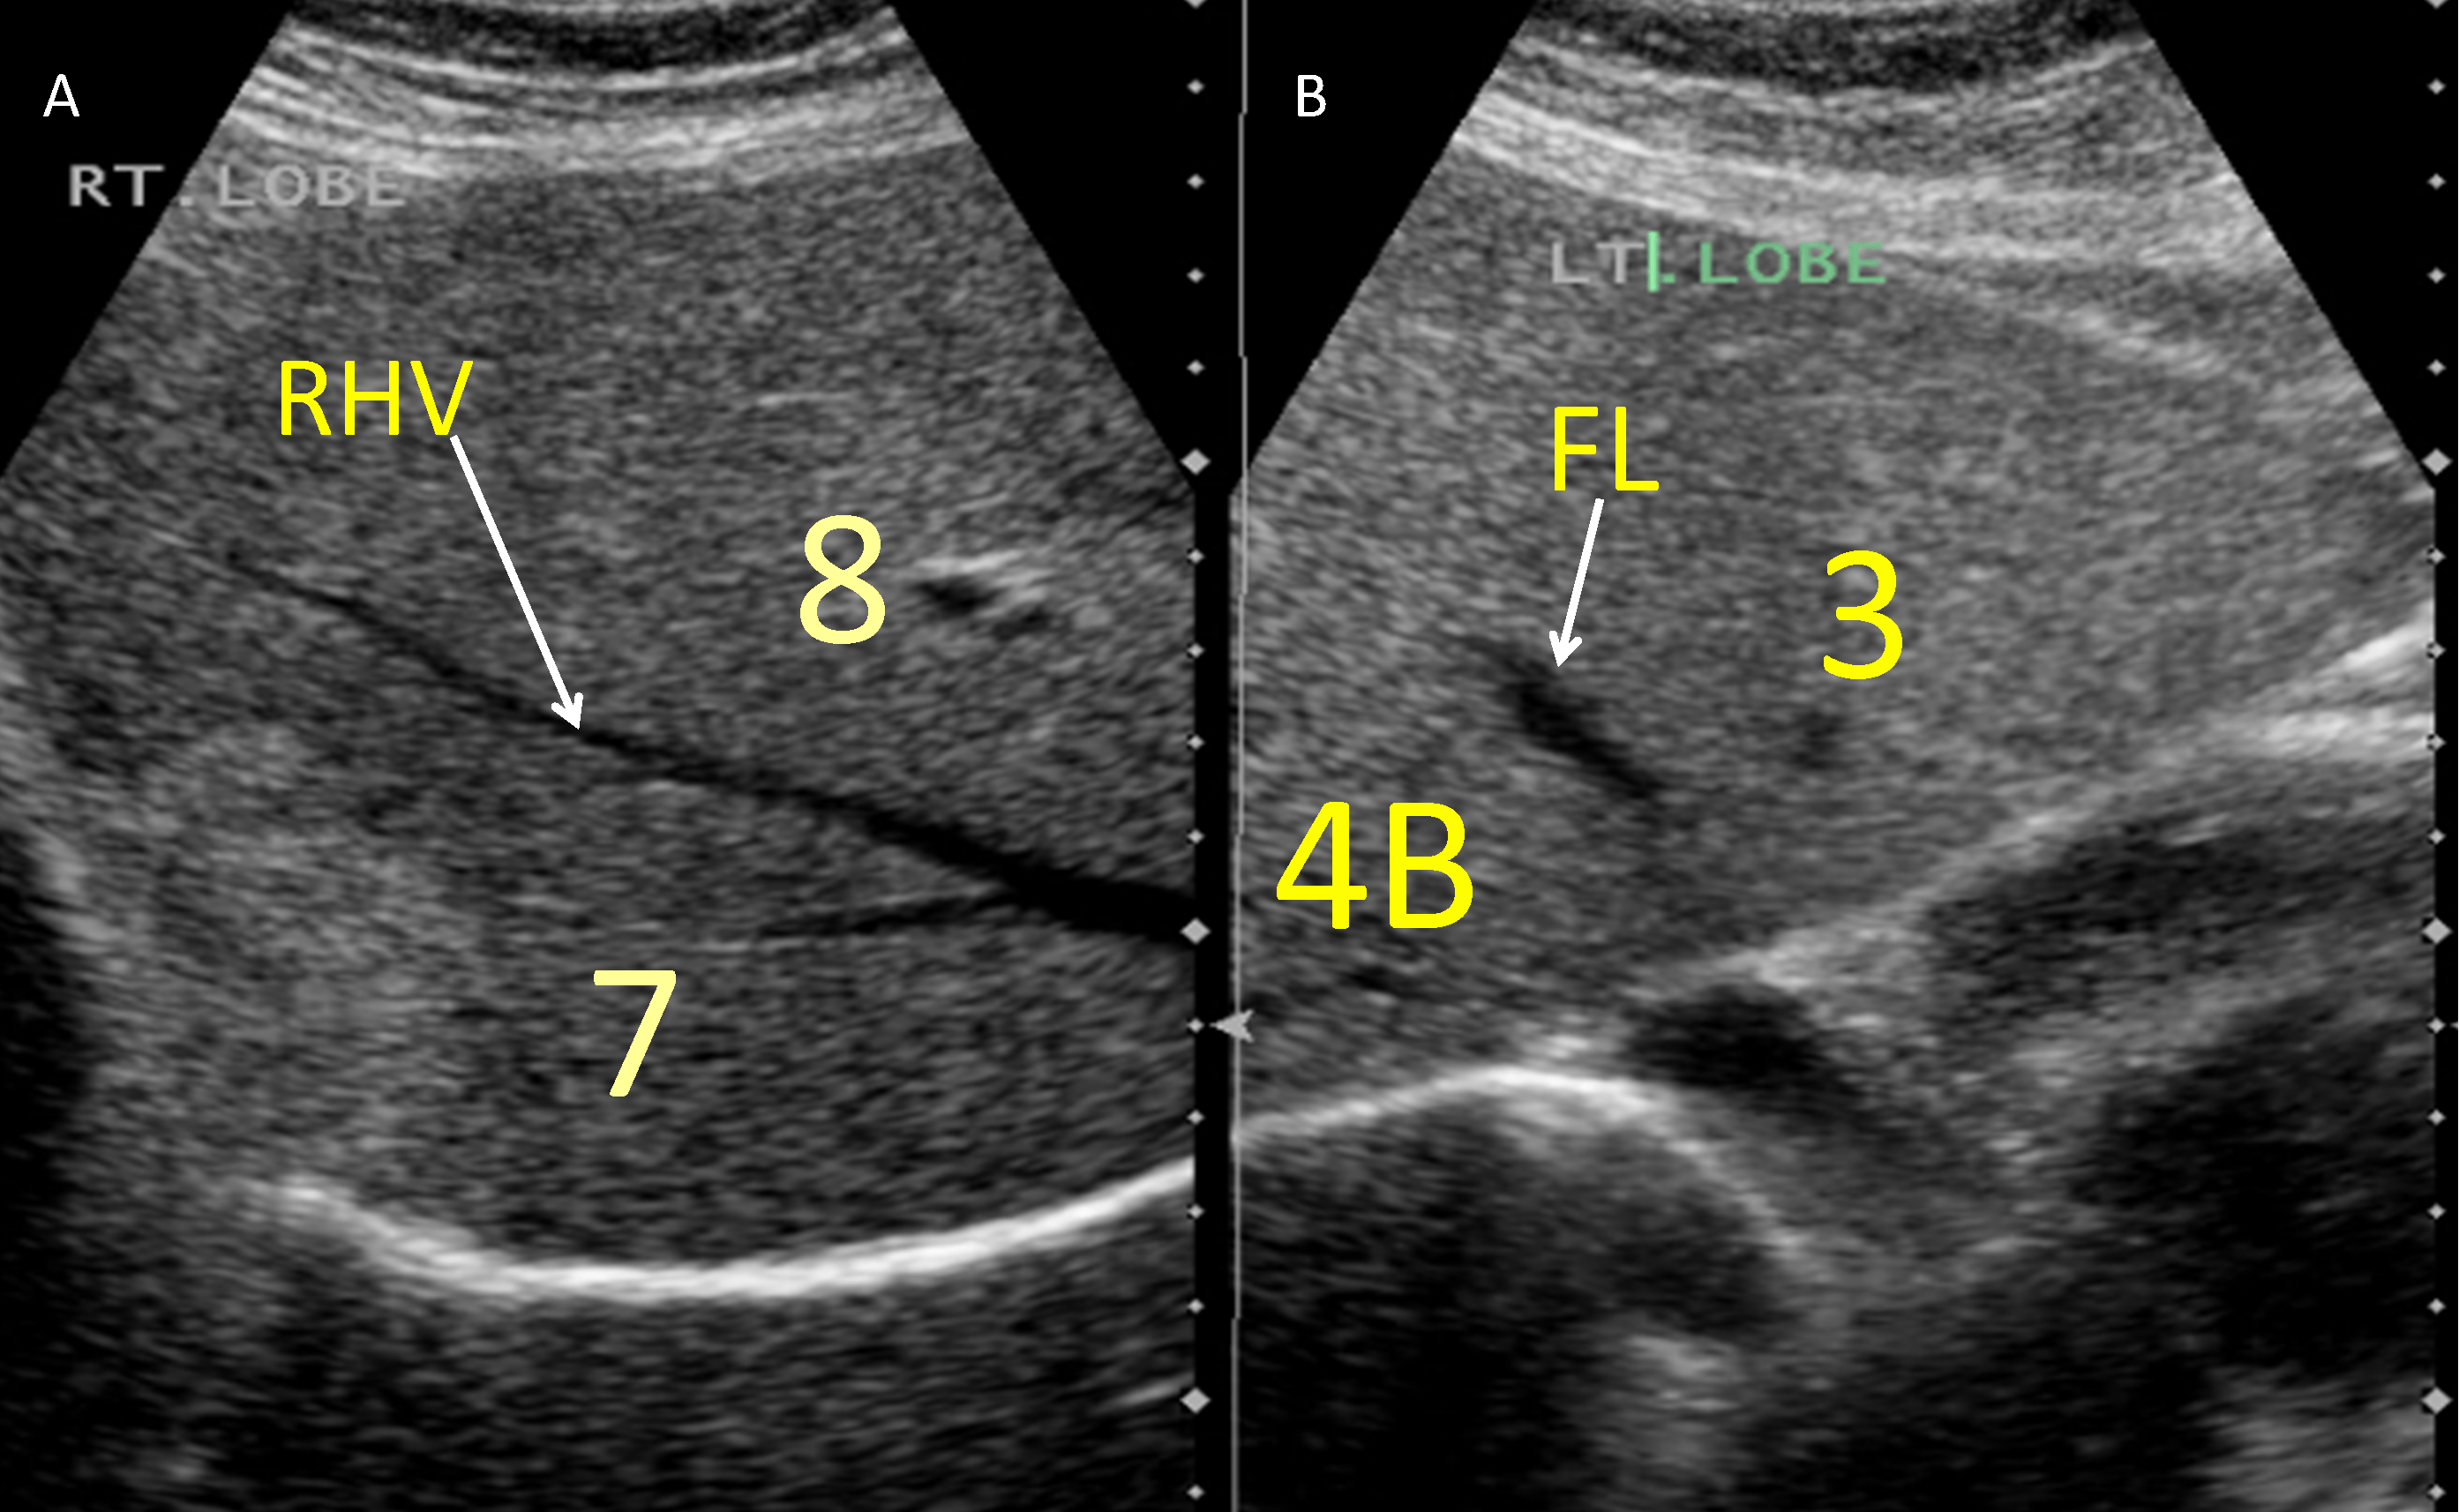

Ultrasound Upper Abdomen Showing Anatomical of Liver . Stock Image Human Anatomy Ultrasound This article provides a beginners guide to ultrasound (pocus), including how ultrasound works and how ultrasound can be used in clinical practice. This ultrasound exam lets you see. This atlas is fortunate to be able to use the interactive anatomy resources developed by vic spitzer, karl reinig, david rubenstein, and. Any pathology found in 2 planes, including measurements and any. Human Anatomy Ultrasound.